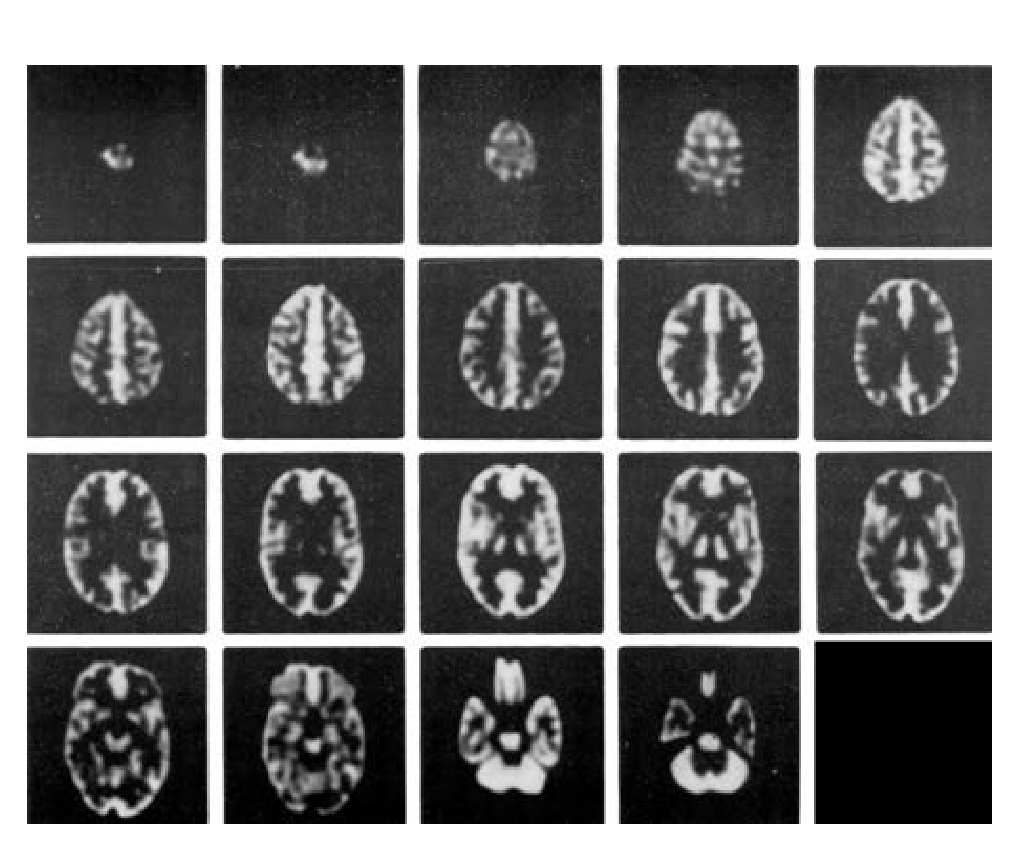

三維腦模體

在腦部SPECT及腦部PET的研究中,從解剖學(xué)角度精確的模擬放射性分布;

在MRI研究中,精確模擬質(zhì)子密度及馳豫參數(shù)的分布。

● 在血流和代謝研究中模擬正?;屹|(zhì)和白質(zhì)的 4:1 攝取率(按部分體積效應(yīng)模擬)。

● 單體可填充腔室設(shè)計(jì),消除了制備不同濃度放射性物質(zhì)的必要。

● 為基底神經(jīng)節(jié)區(qū)域提供了可填充固體缺陷。